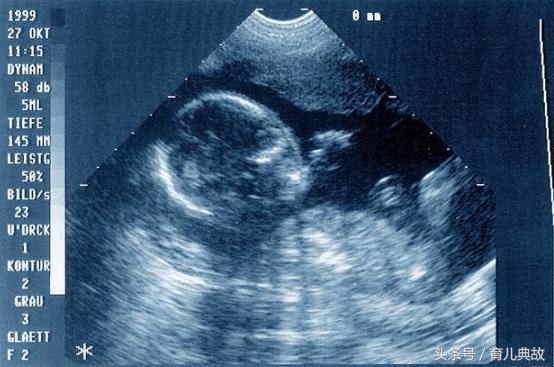

娟姐觉得这样的生活迟早会出问题,可却没想到最先出事的竟是宝宝,去医院检查显示由于营养一直没跟上,胎儿严重的发育不良,导致胎儿保不住。